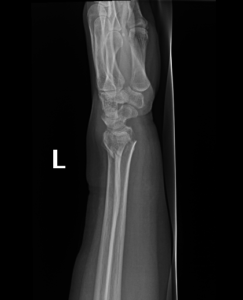

- Wrist Fractures.

Fractures can happen in a variety of ways. Most fractures are due to trauma, with others due to pathological conditions or overuse. Trauma can vary from high-energy injuries such as motor vehicle accidents to low energy injuries such as simple falls.

The human body heals fractures by forming a blood clot that calcifies, connecting the broken pieces of bone. For a good recovery, the bones must be held in the correct position and protected while healing occurs. This may be simply by a plaster or a cast.

if the fracture is displaced, surgery may be needed to put the bone back into the correct position and fix the bone with Plates & screws or nails for adequate healing to occur.